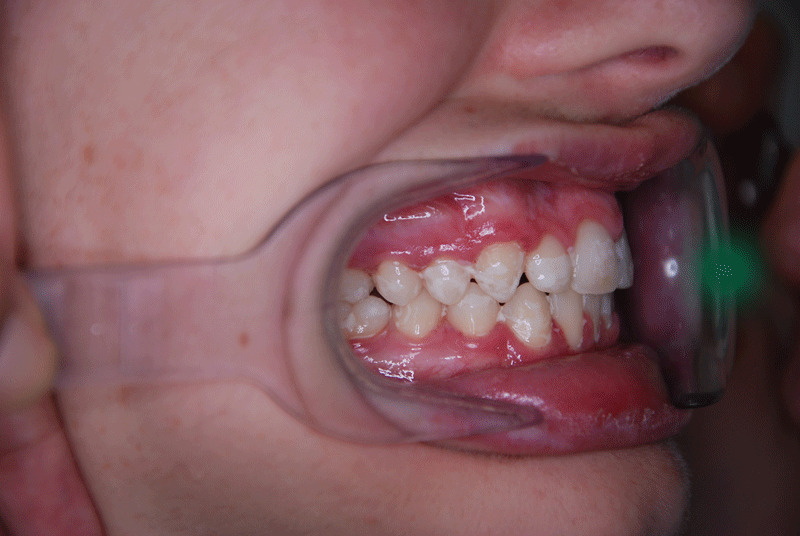

Deep bite before and after side view

Obviously, the overbite is the distance between the edge of the upper and lower central incisors vertically. Clearly, the deep bite considered normal has the upper front teeth exceeding approximately 1/3 of the lower ones.

Particularly, a common cause is when the lower jaw (or maxilla) is small. When this happens, the top teeth look “advanced” and the lower ones continue to emerge and grow until they touch the roof of the mouth.  Obviously, traumatic wounds or ulcers can occur in the palate which can cause considerable discomfort or pain.